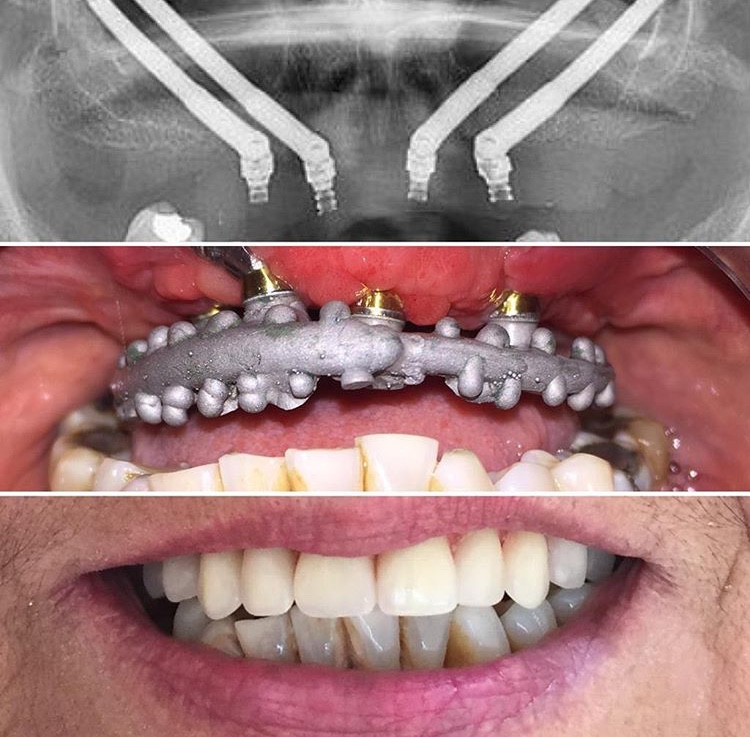

Implantes cigomáticos y rehabilitación dental

Los implantes cigomáticos son una opción para la rehabilitación dental de pacientes con pérdida ósea...